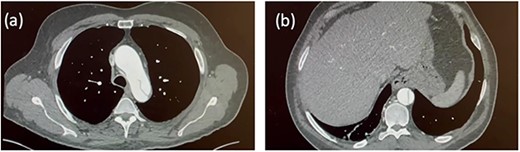

A 54-year-old gentleman with a 30 pack-year history presented to the Emergency Department of a district hospital with sudden, severe upper abdominal pain, per rectum bleeding and vomiting. A computed tomography (CT) scan not only showed bowel ischaemia but also revealed an aortic dissection extending from the lower thoracic aorta into the superior mesenteric artery and bilateral common iliac arteries. An urgent CT aortogram demonstrated that the dissection extended from the left subclavian artery origin and involved the entire descending and abdominal aorta. The patient was diagnosed with a Stanford type B aortic dissection. The ascending aorta measured 45 mm (Fig. 1). The patient was haemodynamically stable and managed conservatively. He was transferred to a tertiary centre hospital for further care.

Initial CT aortogram. Aortic dissection originating from the origin of left subclavian artery with the ascending aorta measuring 45 mm (a). The dissection extends to involve the descending aorta and abdominal aorta (b).